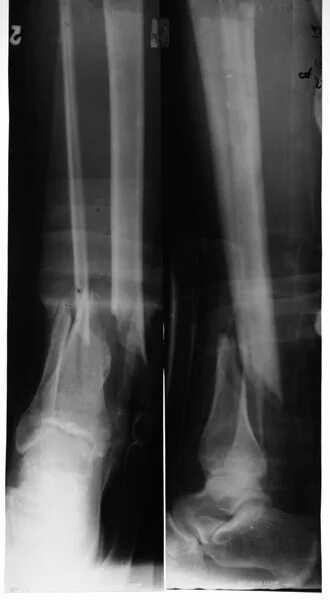

Оскольчатый перелом без смещения